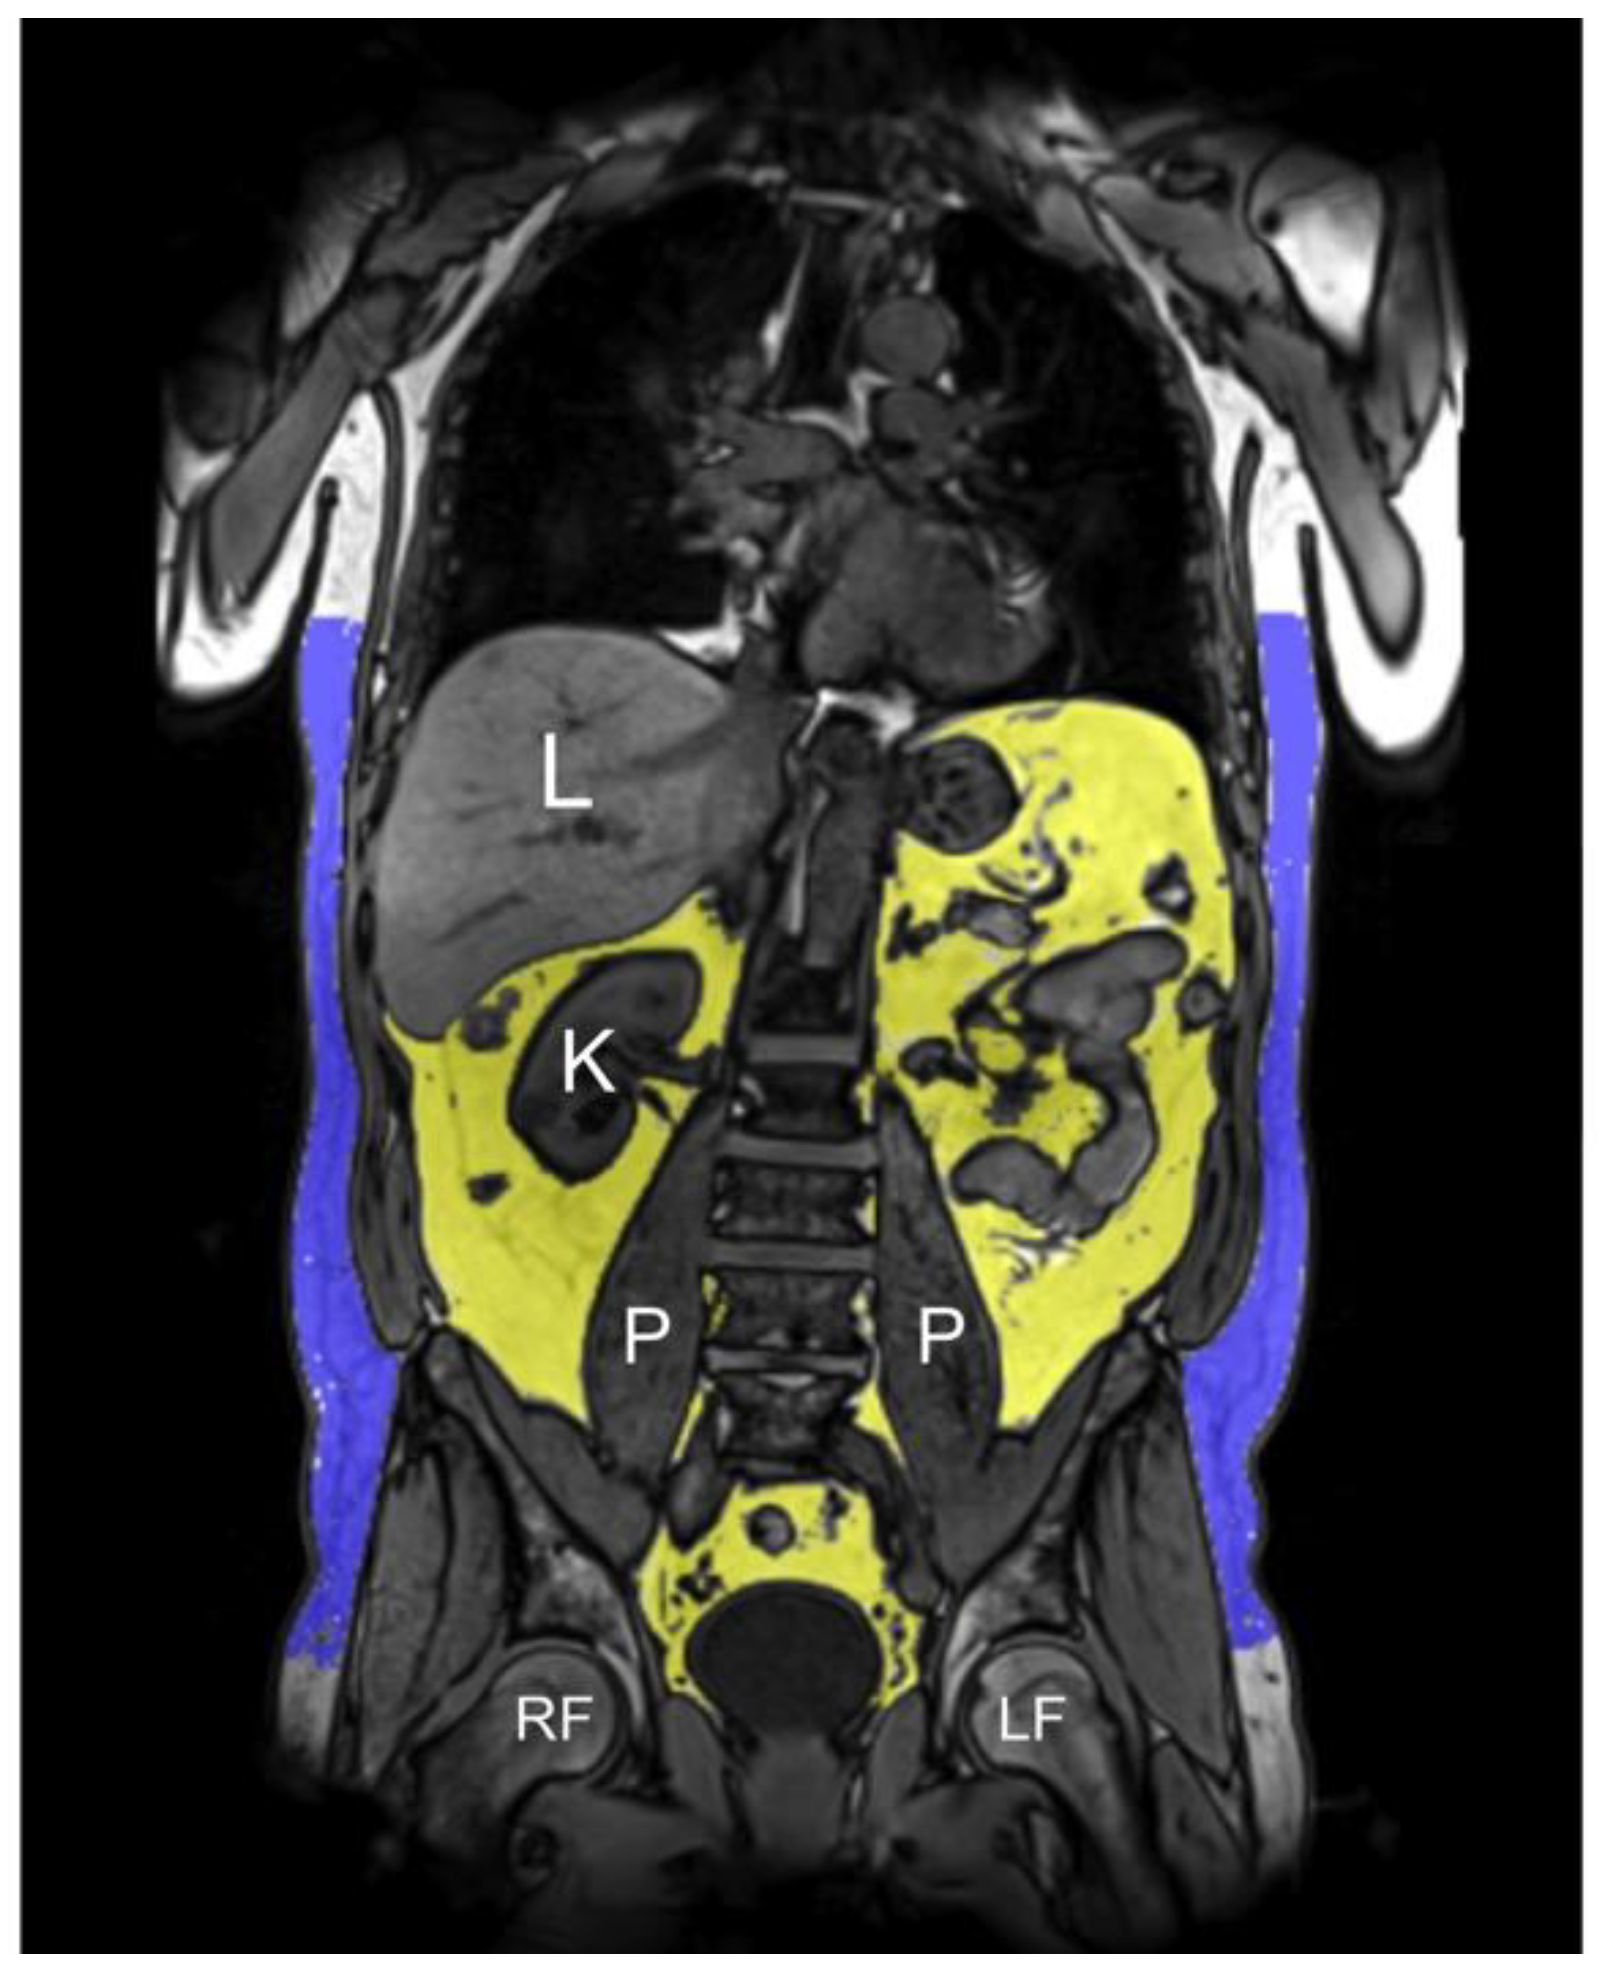

Based on the 3D VIBE-Dixon sequence, a fat selective tomogram was calculated (slice thickness 5 mm at 5 mm increment). Subcutaneous adipose tissue (SAT) from the femoral head to the cardiac apex and VAT from the level of the femoral head to the diaphragm were quantified semi-automatically using an in-house algorithm based on Matlab R2013a [40]. All segmentations were adjusted manually if necessary [27]. TAT was defined as the sum of SAT and VAT (Figure 1). Mean PDFFhepatic was calculated by manually drawing a region of interest on one slice at the level of the portal vein avoiding large vessels and surrounding extrahepatic tissue [41].

Figure 1.

Representative example of the semi-automatic MRI-based assessment of fat depots in a 60-years-old male on reconstructed 3D VIBE-Dixon images (VAT 5.3 L, SAT 7.7 L, TAT 13.0 L). Visceral adipose tissue (VAT, yellow area) and subcutaneous adipose tissue (SAT, blue area) were measured from the diaphragm/cardiac apex to the femoral head; total adipose tissue (TAT) was defined as the sum of VAT and SAT, indicated in liter. L = liver, K = kidney, P = psoas muscle, RF = right femoral head, LF = left femoral head.